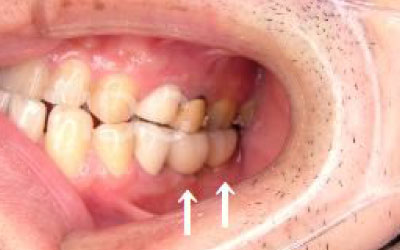

「少しずれた程度なら、噛み合わせを調整したり、小さな詰め物で修正することができます。

しかし、抜けてから数年経過して大きく歯が傾いている場合は、歯並びの矯正を行うか、歯を大きく削ってかぶせ物をする必要があります。

しばらくすると抜けたままでも慣れてきますが、大きな問題が発生します。

2 歯が傾いてくる、落ちてくる

歯はお互いに支え合ってバランスを取っています。ですので、歯が抜けるとその支えがなくなり、抜けた部分の隣の歯が倒れたり、上の歯が下に下がってくることがあります。